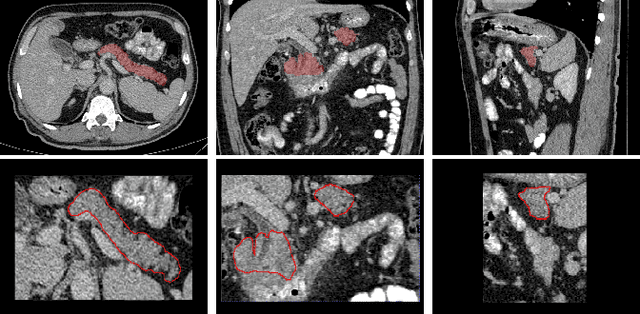

Abstract:Identifying peri-pancreatic edema is a pivotal indicator for identifying disease progression and prognosis, emphasizing the critical need for accurate detection and assessment in pancreatitis diagnosis and management. This study \textit{introduces a novel CT dataset sourced from 255 patients with pancreatic diseases, featuring annotated pancreas segmentation masks and corresponding diagnostic labels for peri-pancreatic edema condition}. With the novel dataset, we first evaluate the efficacy of the \textit{LinTransUNet} model, a linear Transformer based segmentation algorithm, to segment the pancreas accurately from CT imaging data. Then, we use segmented pancreas regions with two distinctive machine learning classifiers to identify existence of peri-pancreatic edema: deep learning-based models and a radiomics-based eXtreme Gradient Boosting (XGBoost). The LinTransUNet achieved promising results, with a dice coefficient of 80.85\%, and mIoU of 68.73\%. Among the nine benchmarked classification models for peri-pancreatic edema detection, \textit{Swin-Tiny} transformer model demonstrated the highest recall of $98.85 \pm 0.42$ and precision of $98.38\pm 0.17$. Comparatively, the radiomics-based XGBoost model achieved an accuracy of $79.61\pm4.04$ and recall of $91.05\pm3.28$, showcasing its potential as a supplementary diagnostic tool given its rapid processing speed and reduced training time. Our code is available \url{https://github.com/NUBagciLab/Peri-Pancreatic-Edema-Detection}.